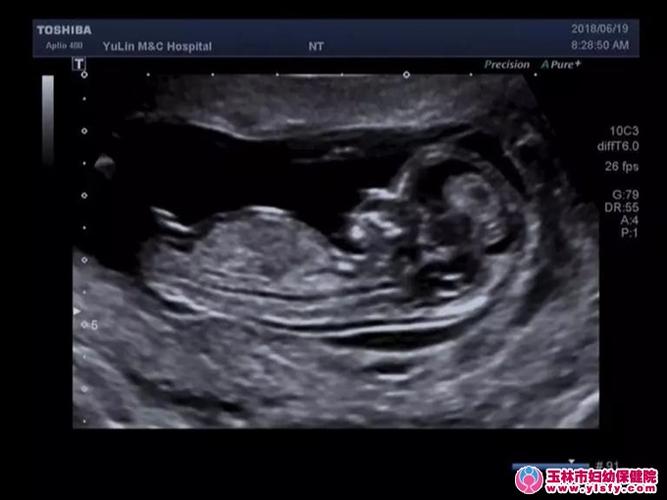

胎儿nt标准测量图片

胎儿nt测量标准切面图

超声nt标准切面图

nt测量标准切面超声图

胎儿nt超声标准切面图